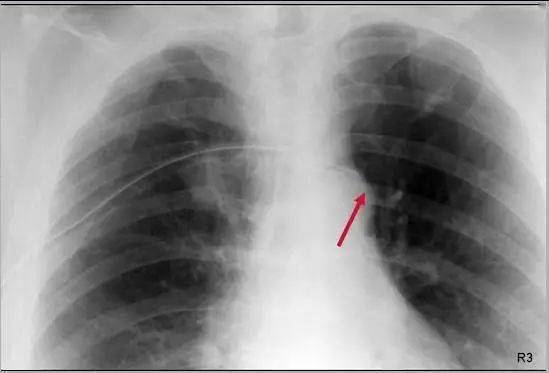

胸腔积液胸片表现图片,胸腔积液胸片典型图片

病例 094:胸腔积液

肋膈角变钝(下图#3)可能表明有胸腔积液

② 胸腔积液